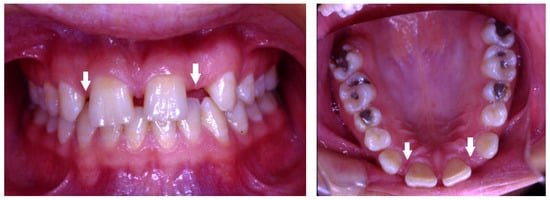

| Supernumerary | Presence of extra teeth more than the full complement of teeth. |

| Ectopic | Eruption of teeth not in their normal position. |